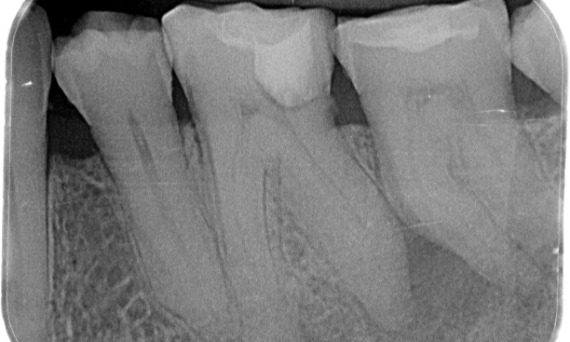

Antes: Radiolucencia periapical asociada principalmente con la raíz distal y pérdida de la lámina dura en la raíz mesial.

Antes: Tras el examen, hubo una lesión de caries relacionada con el primer molar inferior derecho. El examen radiográfico reveló la proximidad de la lesión a la bocina pulpar y, al combinarla con la queja principal, se concluyó un diagnóstico final de pulpitis irreversible crónica.